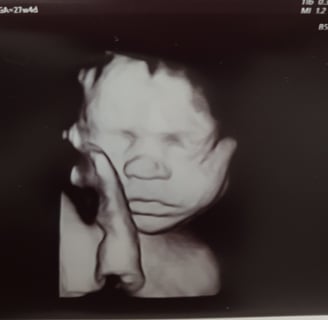

Welkom op de website van Charlie, die zijn geheimen met vrienden en familie wil delen. Een bijzondere tijd nadert!

Ontdek de wereld van Charlie en zijn bijzondere weg naar volwassenheid.

Een speciale plek voor Charlie.